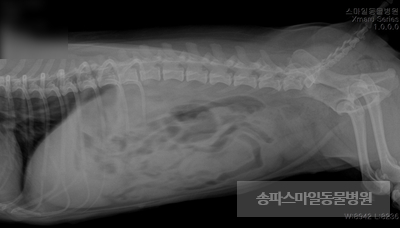

9살 때 볼링 ‘ㄹ’이 생식기에서 피가 나는 증상으로 내원해 주었습니다.

2주 전에 생리가 끝났는데도 소량의 피가 소변에 섞여 나오고 있는 상황이었습니다.

내원 2일 전부터 밥을 먹지 않고 물만 증상이 나타나고 구토, 설사 등의 증상은 없었습니다.

개 생식기의 피가 나오는 증상은 즉시 확인할 수 있었고, 정확한 진단을 위해 추가 검사를 실시했습니다.

초음파 검사상 자궁의 크기가 매우 확장되었으며 자궁 내부의 액체가 고여있는 것으로 확인되었습니다.

강아지 자궁축농증이 진단되었습니다.